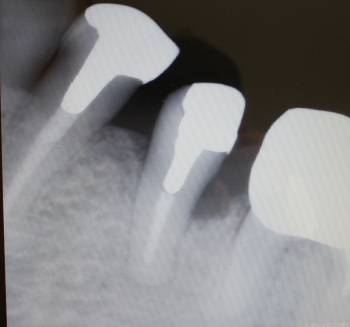

2016年04月06日

骨補填剤充填後のX-ray

2016年07月21日撮影

術後約3.5カ月後

予後良好